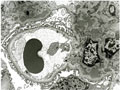

- ★(4)IgA nephropathy

Microscopic findings (HE, high power view): Slight expansion of the mesangium is noted (area within red dotted line).